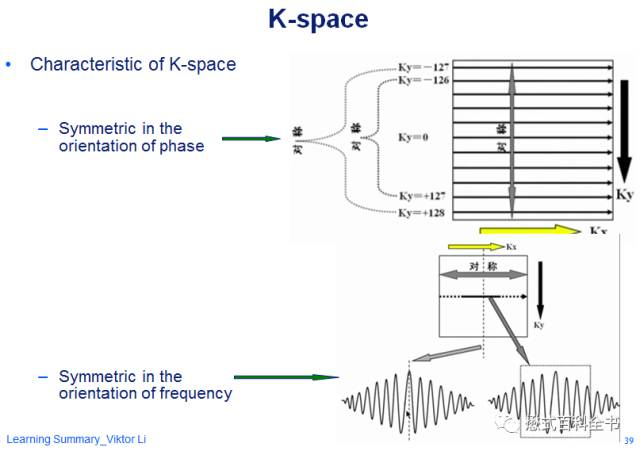

K空间的共轭对称性

首先要了解的K空间的第一个特性就是共轭对称性。

图6:K空间的共轭对称示意图

这里什么叫共轭对称呢?共轭对称的意思是:当一个函数,它的实部为偶函数,虚部为奇函数的时候,并且满足f(x)=f(-x),这个函数就叫共轭对称函数。简单的说就是,把K空间分为四个象限的话,每个对角线都是对称的。

图7-8:K空间共轭对称示意图。

K空间的对称性,其实理解起来也不难。在频率编码方向(Kx)方向,我们采集的是很多信号采样点,模拟成连续信号后,是一个对称的信号变化曲线。

图9:K空间频率编码方向的对称性

图9:K空间频率编码方向的对称性

相位编码方向也是对称的。因为每次相位编码梯度会变化,在K空间中心的时候,不施加相位编码梯度(相位编码梯度为0),在两边分别依次递增相位编码梯度,但是两边的方向相反,所以在相位编方向,K空间也是对称的。

图10:相位编码方向上K空间的对称性